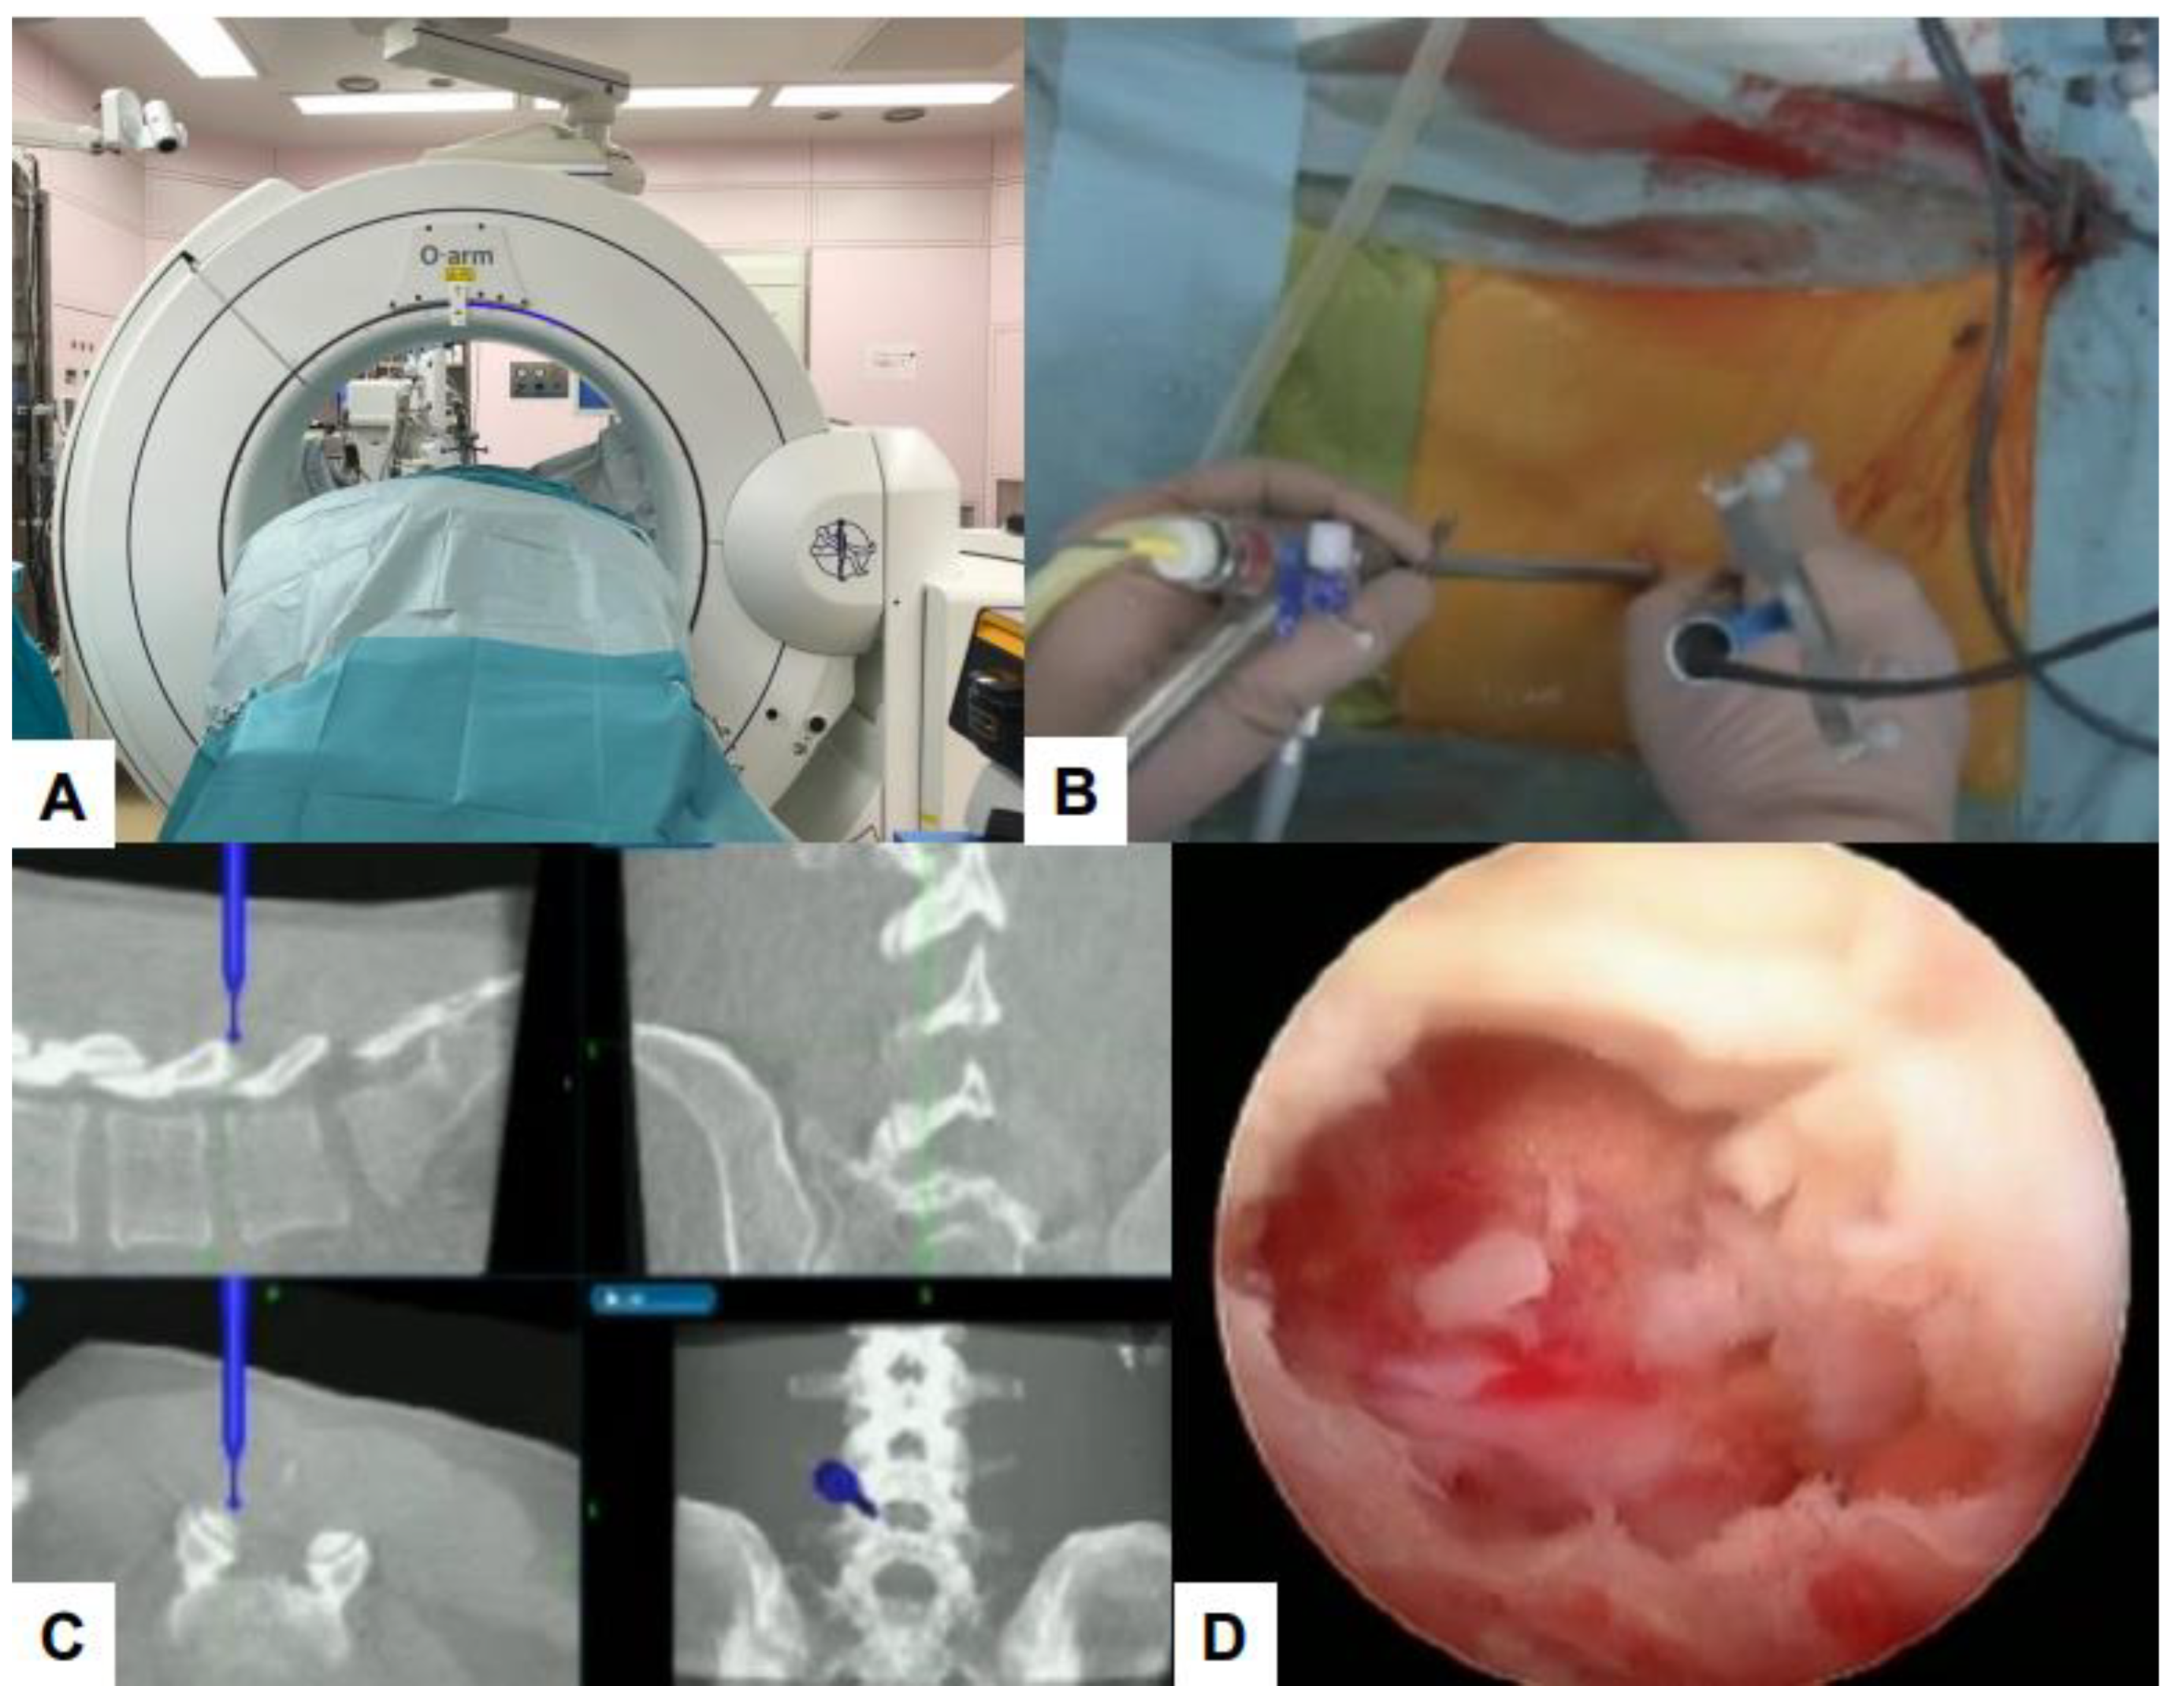

- Zygogiannis, K.; Tanaka, M.; Sake, N.; Arataki, S.; Fujiwara, Y.; Taoka, T.; Uotani, K.; Askar, A.E.K.A.; Chatzikomninos, I. Our C-Arm-Free Minimally Invasive Technique for Spinal Surgery: The Thoracolumbar and Lumbar Spine-Based on Our Experiences. Medicina 2023, 59, 2116. [Google Scholar] [CrossRef] [PubMed]

- Tanaka, M.; Arataki, S.; Mehta, R.; Tsai, T.-T.; Fujiwara, Y.; Uotani, K.; Yamauchi, T. Transtubular Endoscopic Posterolateral Decompression for L5–S1 Lumbar Lateral Disc Herniation. J. Vis. Exp. 2022, 188, e63603. [Google Scholar] [CrossRef]

- Tanaka, M.; Sonawane, S.; Uotani, K.; Fujiwara, Y.; Sessumpun, K.; Yamauchi, T.; Sugihara, S. Percutaneous C-Arm Free O-Arm Navigated Biopsy for Spinal Pathologies: A Technical Note. Diagnostics 2021, 11, 636. [Google Scholar] [CrossRef]